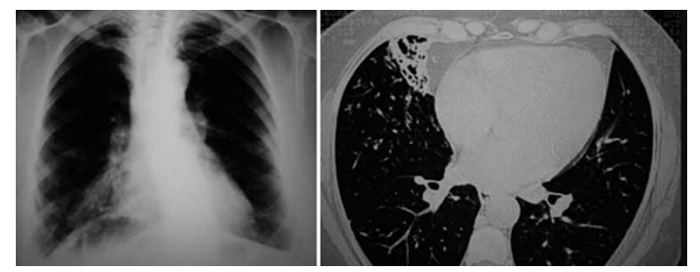

Paciente 37 anos, masculino, com queixa de tosse crônica, expectoração esbranquiçada e diversos episódios

de pneumonias que foram tratadas com antibiótico nos

últimos 5 anos. Refere ter feito investigação para tuberculose, inclusive com “endoscopia dos pulmões”, que

resultou negativa. Apresenta radiografia e tomografia de

tórax recentes a seguir:

(Arquivo pessoal; imagens usadas com autorização)

O diagnóstico e a conduta são, respectivamente: